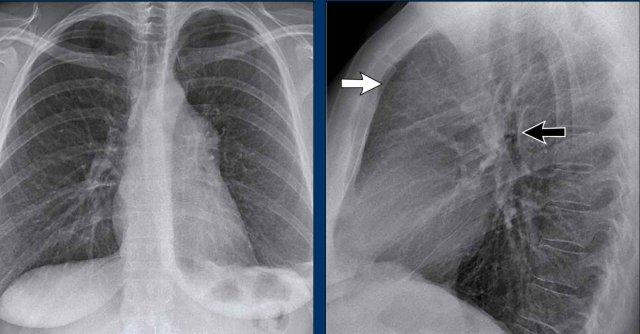

Ca lâm sàng

Bệnh nhân nam 70 tuổi nhập viện sau khi ngã xuống cầu thang, than phiền đau dữ dội vùng hông phải.

Kết quả hình ảnh

- Trên phim X-quang ngực tư thế thẳng (PA), không thấy hình ảnh ngón thứ năm bên phải.

- Trên tư thế nghiêng, có hình ảnh tăng tỷ trọng chiếu lên vùng cột sống ngực dưới.

Chẩn đoán của bạn là gì?

Các dấu hiệu phù hợp với xẹp phổi thùy dưới phải.

Trên tư thế thẳng (PA), lưu ý bờ tim phải có hình dạng bất thường. Động mạch phổi liên thùy phải không được nhìn thấy — do nó không được bao quanh bởi nhu mô phổi thông khí, mà thay vào đó là thùy dưới phải bị xẹp, nằm kề cạnh nhĩ phải.

Trên phim chụp kiểm tra, thùy dưới phải đã nở lại và hình ảnh xẹp phổi đã hồi phục.

Điều này gợi ý rằng xẹp phổi nhiều khả năng là do giảm thông khí sau chấn thương kèm theo nút nhầy.

Cũng ghi nhận trên phim kiểm tra là sự tái xuất hiện của ngón thứ năm bên phải (mũi tên đen) và sự phục hồi bờ tim phải bình thường (mũi tên trắng), xác nhận thùy dưới đã nở lại.